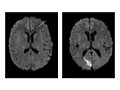

• Todas las estructuras de la cabeza (el cerebro, sus vasos sanguíneos, espacios, nervios y estructuras circundantes) son normales.

• No hay crecimientos anormales, como tumores, dentro o alrededor del cerebro.

• No hay hemorragias, vasos sanguíneos anormales (anomalías arteriovenosas), bolsas anormales de líquido, obstrucción del flujo sanguíneo ni abultamientos en los vasos sanguíneos (aneurisma).

• Hay tumores en el cerebro o en zonas fuera del cerebro, como un neurinoma del acústico.

• Hay hemorragia o hinchazón (edema) en el cerebro o a su alrededor.

• La presencia de zonas anormales en el cerebro puede significar la presencia de ciertas enfermedades, como la enfermedad de Huntington, esclerosis múltiple o enfermedad de Parkinson.

• Hay protuberancias o zonas débiles (aneurismas) o vasos sanguíneos anormales (como una anomalía arteriovenosa).